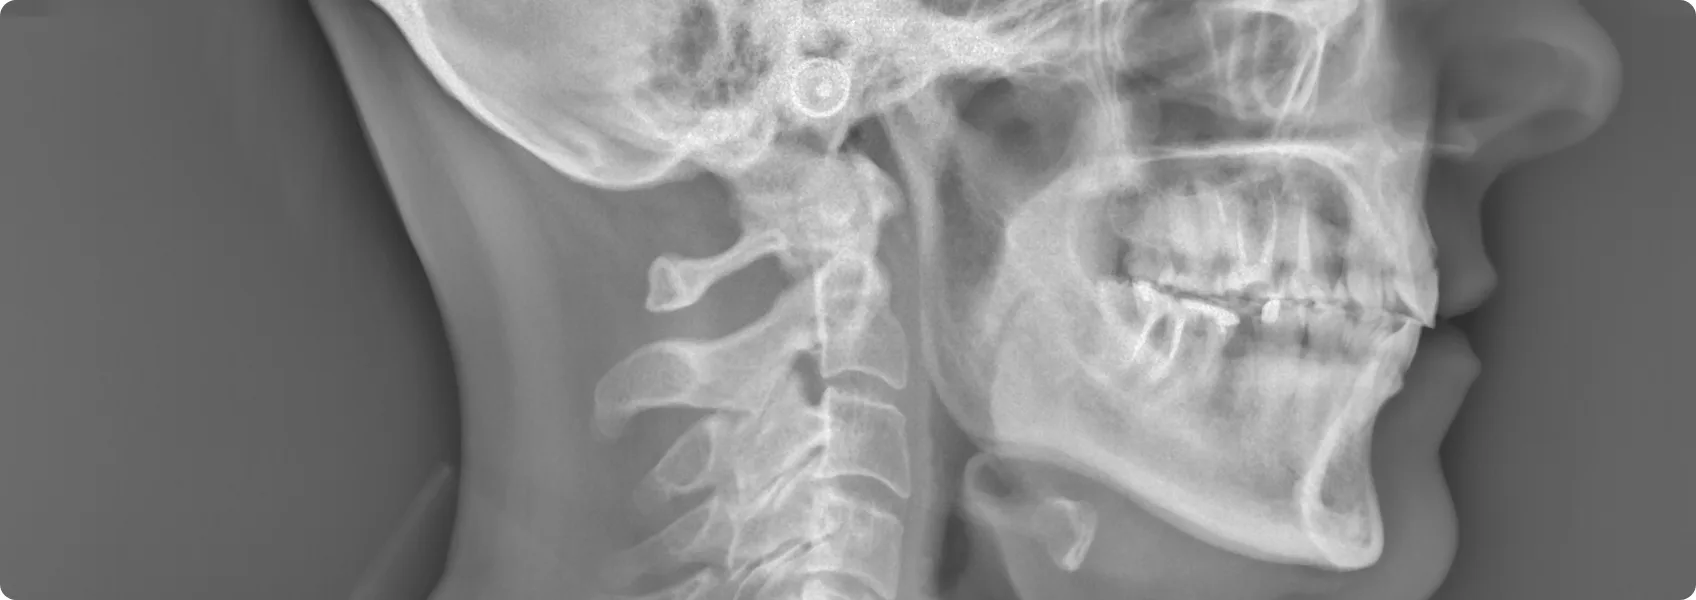

Zaczęliśmy od diagnostyki. Zdjęcia RTG pozwoliły ocenić stan korzeni zębów i kości.

Starty ząb często ma odsłoniętą lub podrażnioną miazgę zębową. RTG pokazuje, czy nastąpiło już zapalenie miazgi, martwica lub inne zmiany wymagające leczenia kanałowego (endodoncji) przed leczeniem protetycznym. Na szczęście, w tym przypadku mogliśmy przystąpić od razu do protetyki.